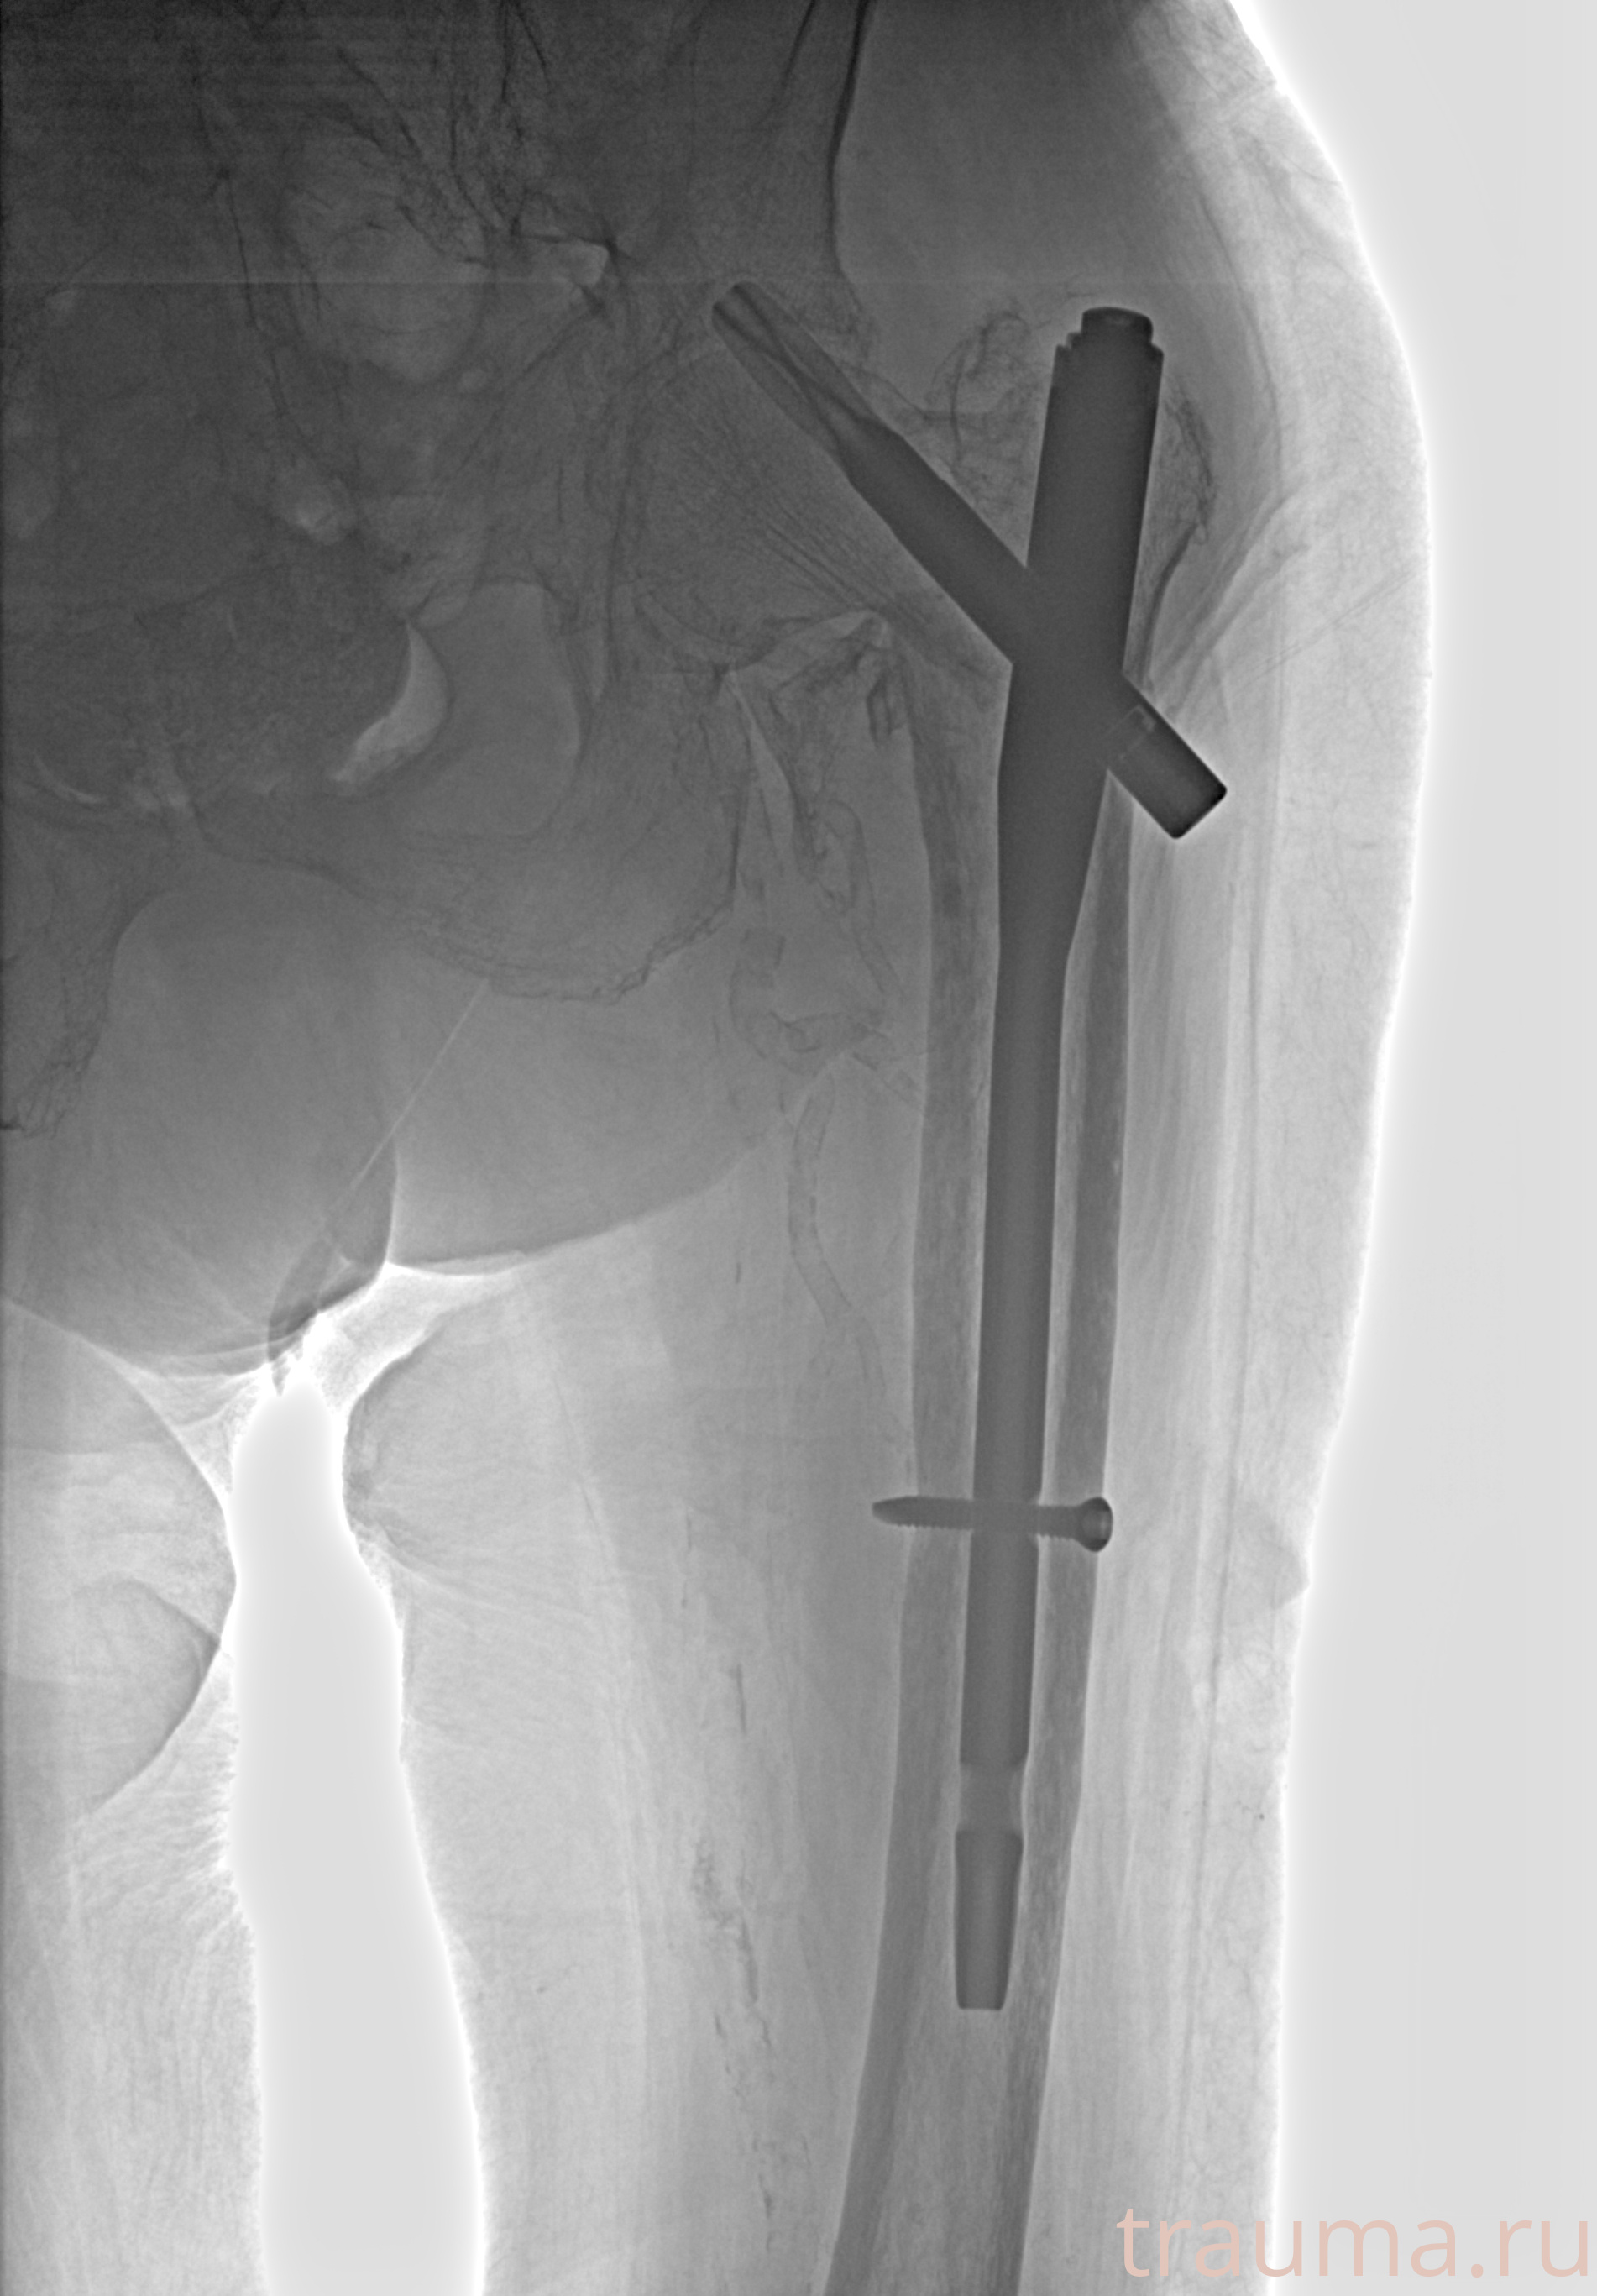

Рентгенограммы

Рентген на дому: по вашему адресу приезжает врач-рентгенолог, травматолог-ортопед с мобильным рентгеновским аппаратом, проводит диагностику травмы или заболевания, делает необходимые рентгенограммы, дает рекомендации по дальнейшему лечению. Получить качественные снимки в домашних условиях возможно благодаря уникальной методике, разработанной МосРентген Центром для института  Склифосовского